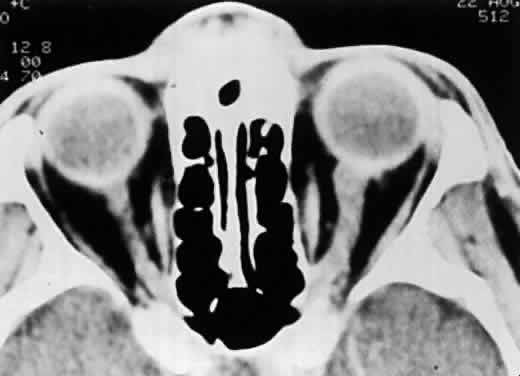

In the absence of direct macular involvement, arterial obstruction, or retinal detachment, decreased central vision that is inconsistent with the associated retinal findings is most likely secondary to optic nerve involvement.28 The presence of optic disc swelling with ARN was noted by early investigators.10 Histopathologic studies have confirmed the presence of intraneural inflammation and necrosis.1,29–31 Both direct inflammation of the optic nerve substance and a secondary ischemic component are believed to produce ARN optic neuropathy, paralleling the pattern of visual dysfunction in the retina. When optic nerve involvement occurs in ARN, an acquired dyschromatopsia, a relative afferent pupillary defect in disproportion to the amount of retinal necrosis, central or arcuate visual field defects, and an enlarged optic nerve sheath can be detected with neuroimaging28,31 (Fig. 14). It often is difficult to distinguish whether visual loss is caused by optic neuropathy or retinal disease in these severely affected patients. An accurate assessment of the incidence of ARN optic neuropathy has not been made. Clinically, optic nerve swelling occurs in a significant number of patients with ARN and may resolve rapidly with therapy.

Fig. 14. CT scan of a patient with unilateral ARN syndrome showing enlarged left optic nerve ipsilateral to the affected eye. (Sergott RC, Belmont JB, Savino PJ et al: Optic nerve involvement in the acute retinal necrosis syndrome. Arch Ophthalmol 103:116, 1985. Reprinted with permission from the American Medical Association)

Computed tomography scans often show optic nerve sheath enlargement on the side affected with ARN.28 Bilateral optic nerve sheath enlargement has been documented despite the presence of unilateral ARN.3 Magnetic resonance imaging (MRI) has shown concurrent lesions of the optic tracts, chiasm, and lateral geniculate body in a patient with ARN, suggesting that infection may spread through the axons of the ganglion cells.3